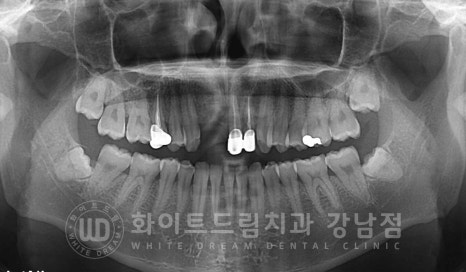

문제가 있던 치아를 발치한 후 임플란트를 식립한 건 아니고

기존 임플란트가 부러져 6개월 전에 제거를 하신 분의 재치료 케이스입니다.

타치과에서 10년 전에 식립한 임플란트가 젓가락을 씹었다고 부러져

제거한 후 한동안 방치를 하신 환자분입니다.

잇몸뼈의 흡수가 조금 진행되어 있어 뼈이식을 동반하여 임플란트를

다시 식립하기로 했고

임플란트 1개을 심어 2개의 치아를 완성하는 방법도 있었으나

이전처럼 2개의 임플란트를 식립하길 원하셨으며

기존의 오래된 옆 21, 22번 크라운도 함께 교체하여 심미성을 회복한 case입니다.

앞니는 보통 어금니 부위보다 골폭이 좁아 직경이 얇은 임플란트를 많이 식립합니다.

보통 어금니는 직경 5mm 정도의 임플란트를 식립하는데

앞니는 남아있는 잇몸뼈의 양에 따라 보통 4-3mm 사이의 임플란트를 식립하게 됩니다.

환자분은 다행히 골이식으로 모자란 잇몸뼈를 커버할 수 있을 것으로 판단되어

직경 4mm의 임플란트를 2대 식립하기로 했습니다.

▲ 환자분의 식립 후 치근단 사진

인접치와 임플란트 사이 일정 공간을 확보하여 잘 식립된 것이 확인됩니다.